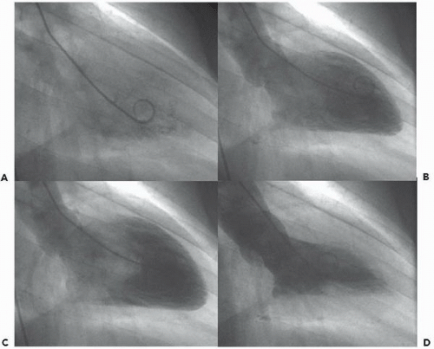

That curly thing (it’s called a “pigtail”) is a catheter sitting in the left ventricle of the heart. Frame D is what it looks like when a healthy heart contracts–if you’ve had damage from a heart attack, you’ll see it here as a section of the chamber that doesn’t contract. Picture source: https://goo.gl/MaS89j